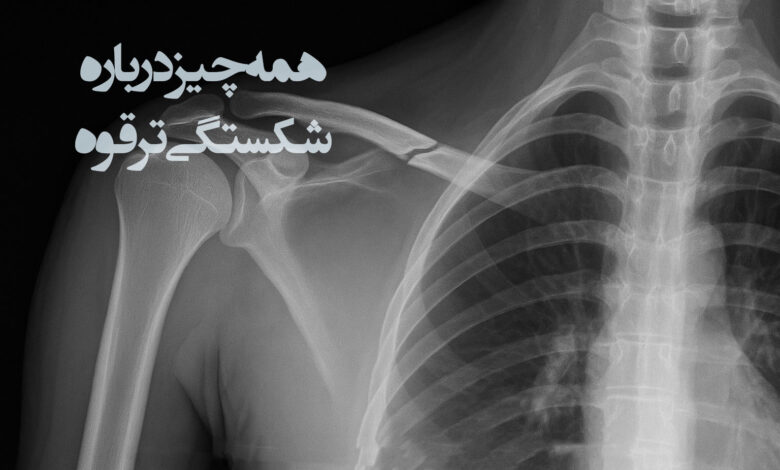

تشخیص شکستگی ترقوه

تشخیص شکستگی ترقوه فرآیندی است که ترکیبی از تجربه پزشکی، مشاهده بالینی و ابزارهای تصویربرداری را در بر میگیرد. این شکستگی که بر اثر ضربه مستقیم، زمین خوردن یا فشار ناگهانی ایجاد میشود، میتواند علائمی مشابه با دیگر آسیبهای شانه یا قفسه سینه داشته باشد. به همین دلیل، تشخیص دقیق آن اهمیت بالایی دارد. پزشک ابتدا با بررسی تاریخچه آسیب، شدت و محل درد، و مشاهده وضعیت کلی بیمار، ارزیابی را آغاز میکند. سپس معاینه دقیق ناحیه برای کشف تورم، تغییر شکل یا حساسیت موضعی انجام میشود. گاهی تغییر وضعیت بازو یا شانه به پزشک نشان میدهد که آیا استخوان جابجا شده است یا خیر. پس از مرحله بالینی، تصویربرداری به ویژه رادیوگرافی، کلید شناسایی محل دقیق و نوع شکستگی است. در موارد پیچیده، سی تی اسکن یا ام آر آی برای دریافت جزییات بیشتر به کار گرفته میشود.

تصویربرداری استاندارد (رادیوگرافی)

تصویربرداری استاندارد با رادیوگرافی، روش اصلی و نخستین برای تأیید تشخیص شکستگی ترقوه است. این تکنیک با استفاده از اشعه ایکس، نمایی واضح از استخوان و محل شکستگی ارائه میدهد. معمولاً تصاویر در دو نما گرفته میشوند تا زاویه، جابجایی و شکل شکستگی به دقت مشخص شود. رادیوگرافی نه تنها سرعت بالایی در انجام دارد، بلکه هزینه کمتری نسبت به سایر روشها دارد و در بیشتر مراکز درمانی به راحتی در دسترس است. کیفیت بالای تصویر و اطلاعات دقیق حاصل از این روش، پزشک را قادر میسازد تا بهترین تصمیم درمانی را بگیرد. در بسیاری از موارد، تنها با همین عکس ساده میتوان تشخیص را قطعی کرد و برنامه درمانی را آغاز نمود.

تصویربرداری پیشرفته در موارد خاص

در برخی موارد شکستگی ترقوه، به ویژه زمانی که آسیب پیچیده یا مشکوک به درگیری مفصل و بافت نرم باشد، استفاده از تصویربرداری پیشرفته ضروری است. سی تی اسکن با ارائه تصاویر سه بعدی و جزئیات بسیار دقیق از محل شکستگی، به ویژه برای بررسی جابجایی و قطعات خرد شده، کاربرد دارد. ام آر آی نیز در ارزیابی آسیبهای بافت نرم، رباطها و عروق اطراف استخوان، نقش برجستهای ایفا میکند. این روشها گرانتر و زمانبرتر از رادیوگرافی هستند، اما دقت بالای آنها در تصمیمگیری درمانی، به ویژه قبل از جراحی، اهمیت بالایی دارد. انتخاب میان این دو روش بر اساس نظر پزشک و وضعیت بالینی بیمار انجام میشود.